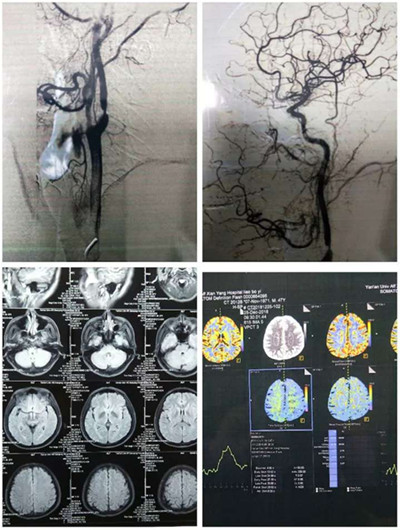

患者廖某,男,47歲,因言語不利,右側肢體活動不靈10小時入住我院神經內科治療,入院診斷為左側多發腦梗塞。CT顯示:左側腦室旁多發腦梗塞。B超顯示:左側頸動脈斑塊形成。為進一步明確病因,行腦血管造影,結果顯示左側頸內動脈起始部斑塊附壁,管腔狹窄80%。

姚曉峰副院長結合病史、檢查結果會診后建議行頸動脈內膜剝脫術(CEA)。經患者同意后轉入神經外科三病區(血管/介入科)。2019年1月3日由姚曉峰副院長主刀,宋波、張家偉責任總醫師作為一助的共同努力下,經過1個多小時順利完成我院第一例頸動脈內膜剝脫術。經術后觀察治療,2019年1月8日患者言語、肢體活動完全恢復正常,痊愈出院。